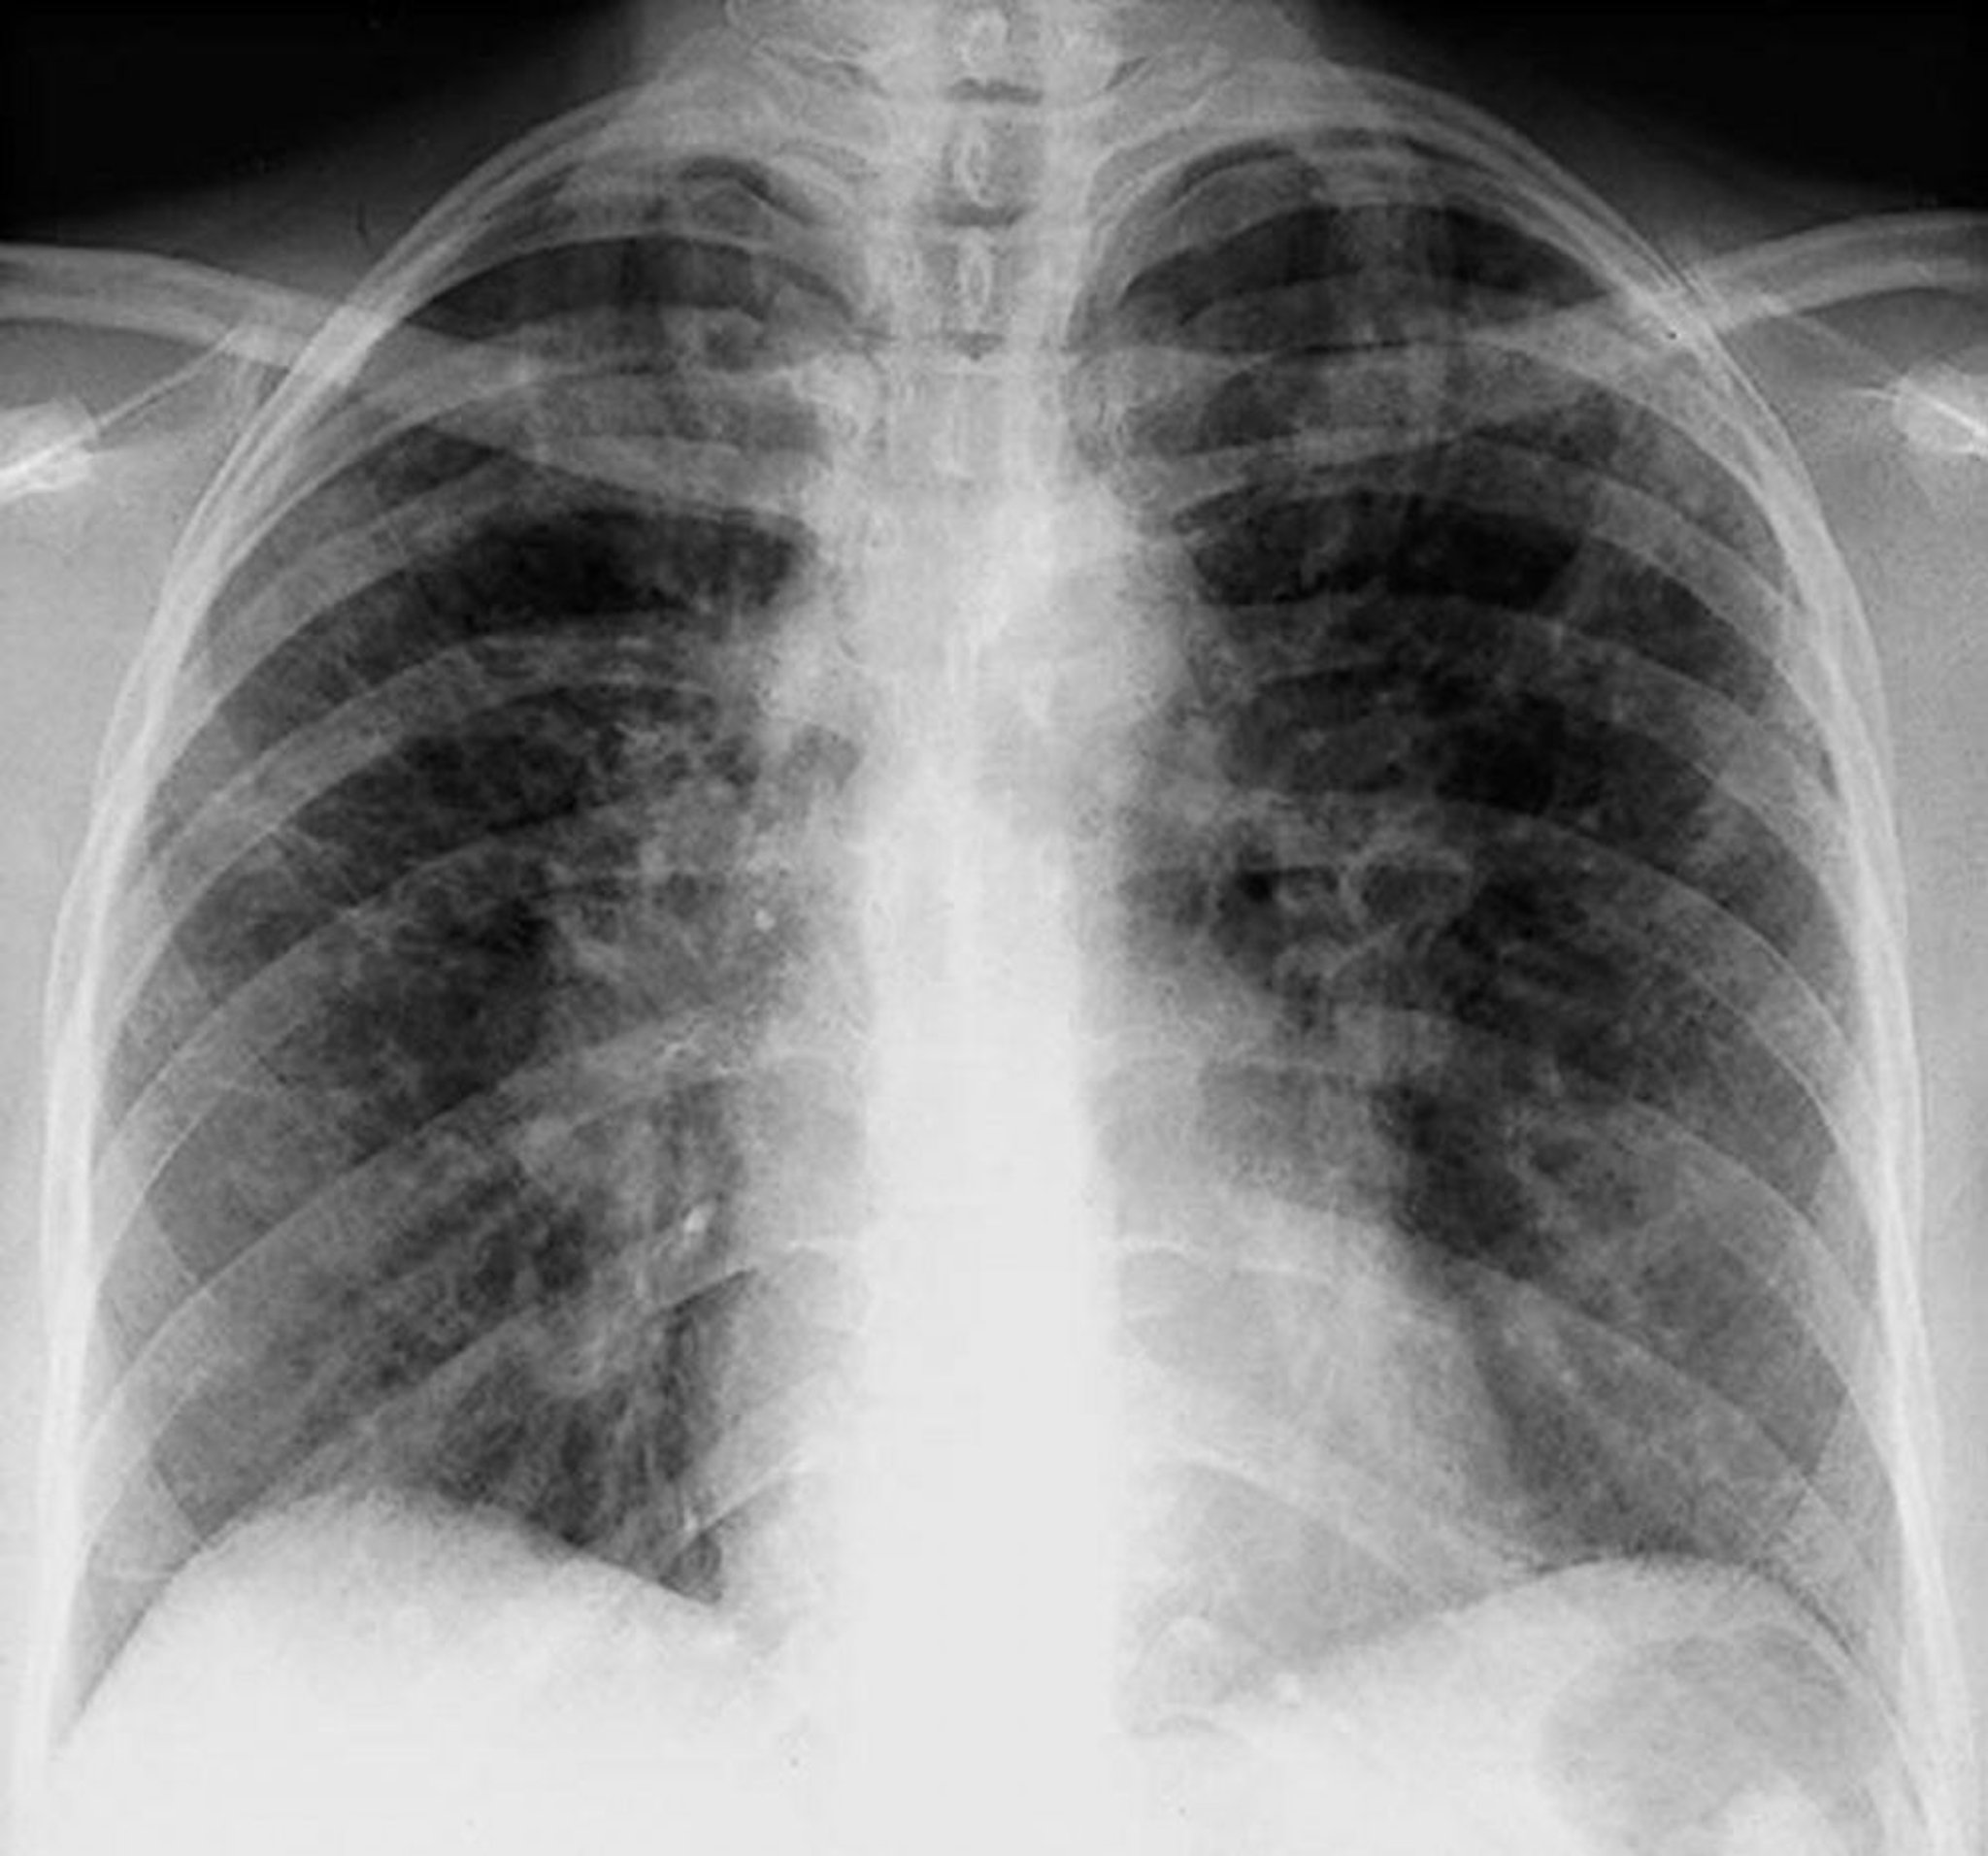

Sarcoidosi (stadio II)

Adenopatie ilari bilaterali con opacità interstiziali nella sarcoidosi al II stadio.

By permission of the publisher. Da Tanoue L, Elias J. In Bone's Atlas of Pulmonary and Critical Care Medicine. Edited by J Crapo. Philadelphia, Current Medicine, 2005.